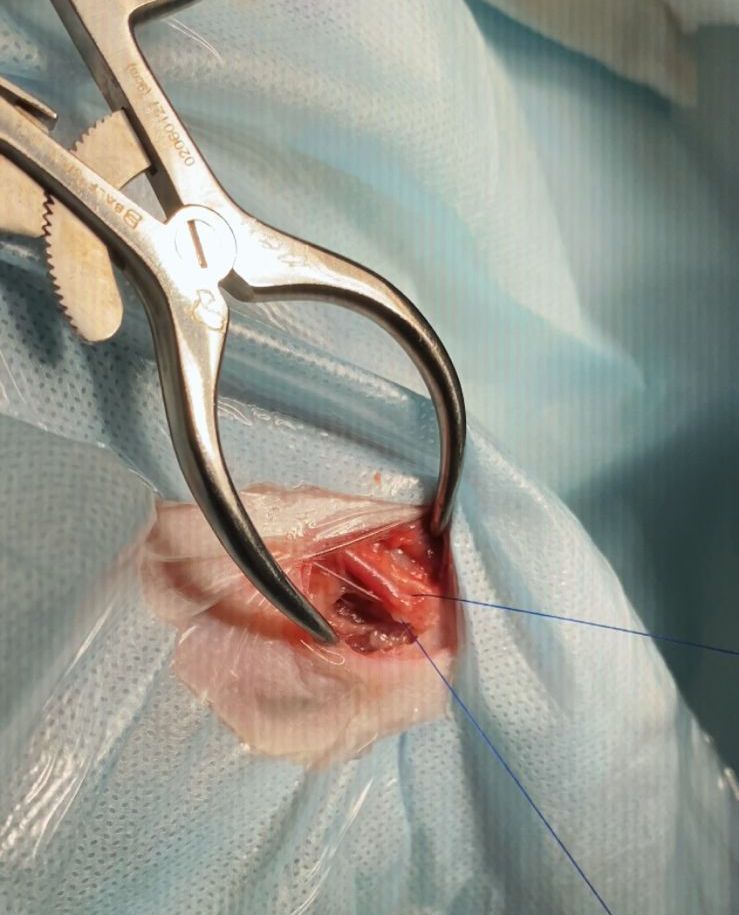

В бедренную артерию устанавливают интродьюсер размером 4–5 Fr. Сосудистым катетером Cobra или другим под флюороскопическим контролем осуществляют катетеризацию общей печеночной артерии через чревную. Затем проводят селективную артериографию для выявления ветвей печеночной мальформации. Далее через микрокатетер, который размещают в приносящих артериях, поочередно вводят эмболизирующий агент. В литературе рекомендуют использовать смесь цианакрилата (NBCA) и липиодола. Липиодол – контрастное масляное вещество, которое способствует замедлению процесса полимеризации клея. Смесь вводят поочередно в каждую приносящую ветвь, регулярно проводя ангиографию. Процедуру завершают, когда в сосудах «гнезда» мальформации больше не наблюдается тока крови.

Для эмболизации артериовенозной мальформации печени (рис. 4) у 5-месячной собаки весом 2,7 кг автор статьи использовал спирали, а также коллагеновую губку и клей (3M Vetbond). Сосудистый доступ осуществлялся через бедренную артерию, в которую был установлен интродьюсер 4 Fr (рис. 5). Катетеризация печеночной артерии проводилась катетером Cobra, 4 Fr (рис 6.) В трех наиболее крупных ветвях приносящих артерий были размещены спирали, однако сильный ток крови в сосудах «гнезда» после размещения спиралей сохранялся. Из коллагеновой губки, контрастного вещества («Ультравист») и физраствора была приготовлена смесь в объеме 1,0 мл, которая была введена через катетер 4 Fr, размещенный в области бифуркации приносящих артерий «гнезда». Это снизило риск миграции клея в портальную вену и нецелевой эмболизации. После этого по катетеру был введен клей 3M Vetbond. По окончании манипуляции в сосудах «гнезда» мальформации не отмечалось наличия тока крови.